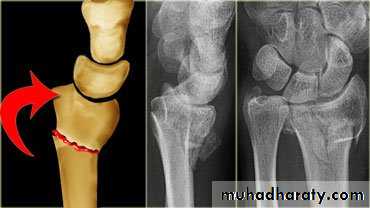

Dr. Saad Abdul AzizColle’s fracture

is a transverse fracture of the distal radius just above the wrist with dorsal displacement of the distal fragment.It’s the most common of all fractures in older people.

fall on outstretched hand, its either undisplaced or displaced .In displaced fracture the distal fragment collapses into extension, dorsal displacement, radial tilt and shortening.

X-rays: AP&Lat. Views